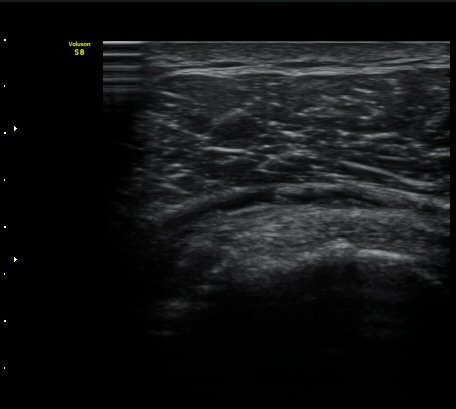

±Ø»ó°Ç Á¾´Ü¸é°Ë»ç½Ã ±Ø»ó°Ç ºÎÂøºÎ¿¡ Àú¿¡ÄÚ ºÎÁ¾°ú ¹Ì¼¼ÇÑ °Ç ¿¬°á¼º ¼Ò½ÇÀÌ

°üÂûµÊ (±×¸² 1, 2, 3 )